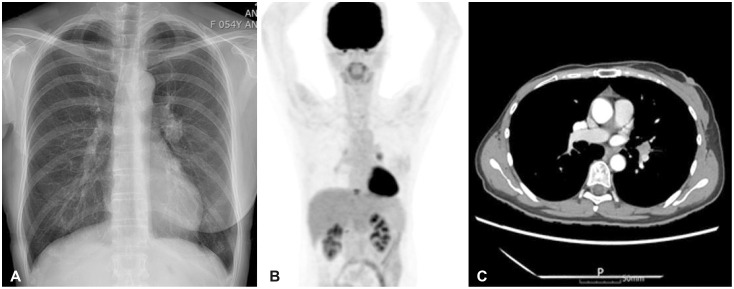

This case introduces the differential diagnosis of a well-enhancing lesion in the prepontine cistern of a 55-year-old female patient who was diagnosed with recurrent metastatic breast cancer. The patient was diagnosed with breast cancer 11 years ago and underwent a mastectomy and subsequent adjuvant therapy. Tamoxifen had been given for 5 years, and the treatment was completed. Five years after, she found a lung nodule on her routine chest X-ray examination. Based on her past medical history, systemic cancer work-up was done and it revealed multiple lesions in T10 vertebra, lungs, and mediastinal lymph nodes. Trans-bronchial needle aspiration was performed and the biopsy was a metastatic breast cancer. Brain MRI was taken as she was complaining of headache and it showed a well-defined, ovoid enhancing 0.9-cm nodule in the right prepontine cistern. Neuro-oncology tumor board evaluated the lesion as more likely to be an asymptomatic neurogenic tumor rather than metastasis based on radiological features including brainstem surfaced location, slightly high signal intensity on T2-weighted image and no diffusion restriction. To rule out leptomeningeal metastasis, a serial cerebrospinal fluid cytology examination (×3) was done and negative for malignant cells. Follow-up brain MRIs of 2 and 9 months showed no significant changes in the pre-pontine enhancing lesion.